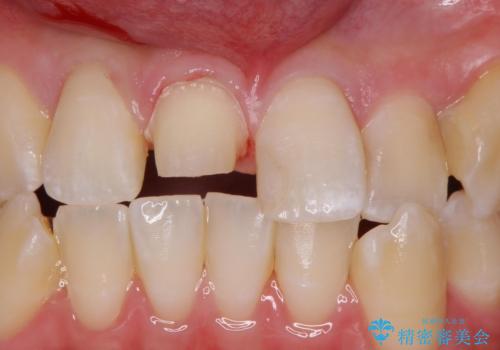

前歯の色が気になる。オールセラミッククラウンでのやり替え

- 前歯のかぶせ物の色が気になるとのことで来院された患者様です。

セラミッククラウンで作り変えていきます。

- 右上1: 仮歯/11,000円、ジルコニアクラウン(スタンダード)/121,000円 合計132,000円(税込)費用は治療当時の料金となります